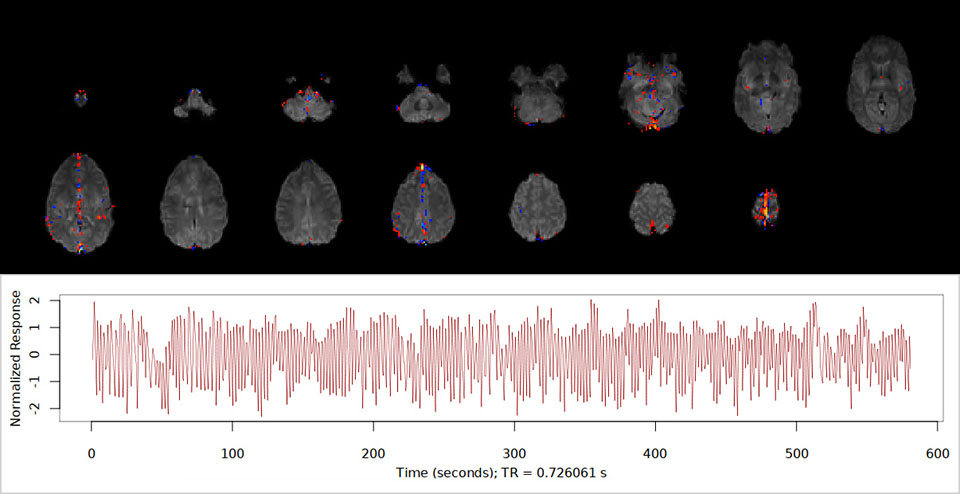

fMRI of viewing and matching facial expressions

BOLD fMRI activation, depicted in color, of left anterior insula (MNI plane z = 8 mm) in a single subject by a contrast between viewing and matching faces with negative emotion (angry, sad, scared) versus happy faces. The voxelwise threshold is p < 0.001, and colored voxels survive false discovery rate correction to p < 0.05. The activated voxels in color are overlaid on the subject's own 3D-TFE image displayed in grayscale, after transforming the data to MNI space. The fMRI pulse sequence was a single shot FFE echo planar acquisition using MultiBand SENSE factor 6, dS SENSE factor 1, isotropic voxel size 2.4 mm, 60 transverse slices, TR 950 ms, TE 30 ms, flip angle 52 degrees, 517 dynamic scans, total scan duration 8:21 minutes. Image provided by James M. Bjork, PhD, Associate Professor of Psychiatry at VCU.

MultiBand SENSE helps Dr. Steinberg increase temporal resolution in BOLD fMRI. “In event-related fMRI, it´s favorable to get very frequent acquisitions, in order to obtain a better sampling of the brain´s physiological activity over time. With a MultiBand factor of 6 we can get a TR of only 800 ms. Without MultiBand, our TR would be much higher. So MultiBand SENSE gives us a huge improvement in SNR, as it allows us to get more acquisitions during the same period of time. And time is of the essence, because most subjects cannot tolerate staying in the scanner for too long while performing an fMRI task.”

“For children, we try to keep the scans to 5 minutes each. We try to get 8 minutes for adults, but certainly no scan is longer than 10 minutes. Within these limited time periods, MultiBand SENSE has greatly improved our temporal resolution, while maintaining an excellent isotropic spatial resolution of 2.4 mm and 60 slices; that´s excellent full brain coverage.”

Dr. Steinberg adds that before using MultiBand SENSE, fewer acquisitions were being made with a poor temporal resolution of 2,300 milliseconds. However, using MultiBand SENSE now, “we’re able to improve the temporal resolution, SNR, spatial resolution, and still get full brain coverage, without making time too long for the research subject.”